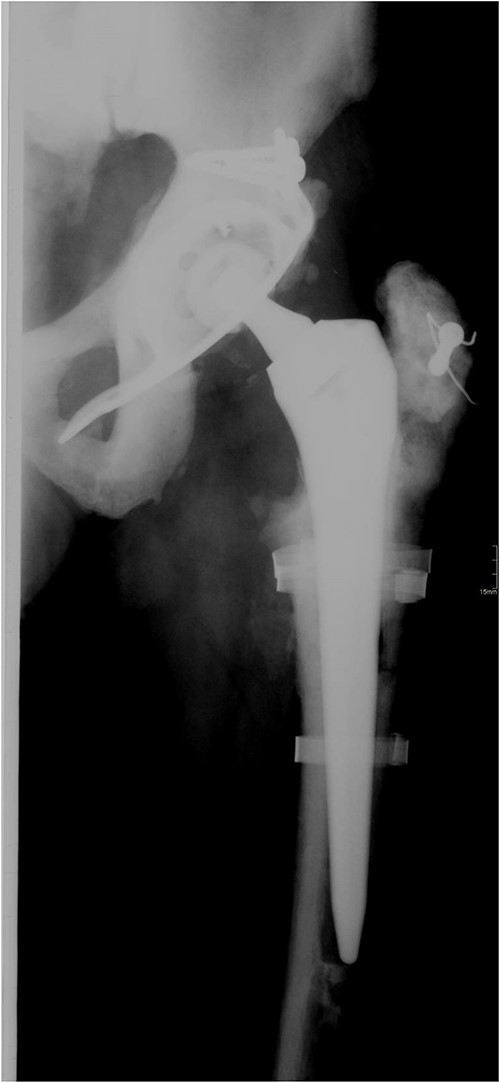

A 73-year-old man showed himself to our hospital in 1989, complaining of left hip pain. X-ray imaging revealed advanced osteoarthritis of the left hip as well as skeletal abnormalities pathognomonic for osteopetrosis. Following earlier intertrochanteric osteotomies carried out elsewhere, there was osteosynthetic material present in the right femur. A cementless isoelastic total hip arthroplasty (THA) was performed (Fig. 1). The greater trochanter was fractured and repaired with screws and cerclages.

Isoelastic uncemented hip arthroplasty. Broken trochanteric part was fixed with cerclage wires and screws.